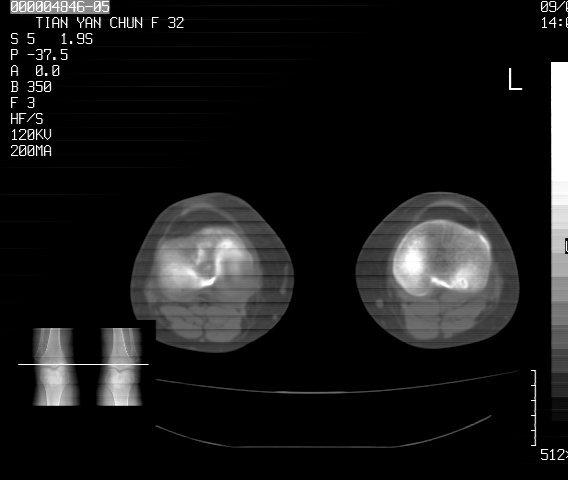

标题: CT18487:请会诊,女32岁,左膝疼痛数日 [打印本页]

标题: CT18487:请会诊,女32岁,左膝疼痛数日

关节面软骨有硬化环考虑退行性变

定位片可见髁间棘骨质增生,支持膝关节退行性变。

定位片可见髁间棘骨质增生,支持膝关节退行性变。建议mri 检查

考虑骨性关节炎